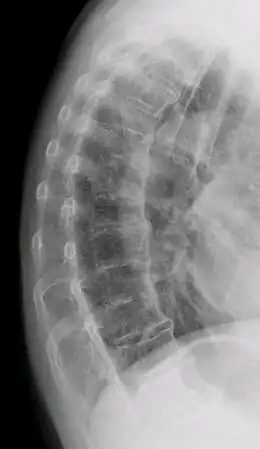

La maladie de Forestier ou maladie de Forestier et Rotés-Querol est une hyperostose vertébrale exubérante en « flamme de bougie » des faces antéro-latérale des corps vertébraux qui entraîne des raideurs du dos ou du cou et parfois une dysphagie. Initialement décrite par lui, cette maladie prit le nom du médecin français Jacques Forestier[1], parfois associé à celui de Jaume Rotés Querol, rhumatologue né en Catalogne.

Elle se traduit par des ponts osseux, initialement entre les vertèbres dorsales, s'étendant progressivement aux vertèbres lombaires et aux vertèbres cervicales. Elle touche parfois les articulations des hanches et peut provoquer un rétrécissement du canal rachidien qui comprime les racines des nerfs sciatiques. La plupart du temps elle est bien tolérée et n'entraîne qu'une limitation peu douloureuse des articulations et de la mobilité de la colonne vertébrale.

C’est surtout la particularité de l’aspect radiologique qui permettait de distinguer ces patients. La « coulée » osseuse antérieure, continue à l’étage dorsal, devenait discontinue sur les rachis lombaire et cervical sans altération de la hauteur du disque. Il n’y avait pas, contrairement à ce qu’on rencontre dans la SPA, d’arthrite sacro-iliaque.